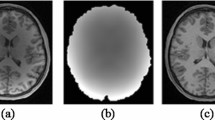

In this study we propose a novel correction scheme that filters Magnetic Resonance Images data, by using a modified Linear Minimum Mean Square Error (LMMSE) estimator which takes into account the joint information of the local features. A closed-form analytical solution for our estimator is presented and it proves to make the filtering process far simpler and faster than other estimation techniques that rely on iterative optimization scheme and require multiple data samples. An experimental validation of our correction scheme was carried out through large scale experiments using both clinical and synthetic MR images, artificially corrupted with rician noise of σ varying from 1 to 40. These noisy images were filtered using our proposed method against the classical LMMSE, the Non-Local Means filter and the Nonlocality-Reinforced Convolutional Neural Networks (NRCNN) techniques. The results show an outstanding performance of our proposed method, given the fact that from σ ≈ 12 onwards, the proposed method outperforms all other methods. Another attention-grabbing feature of our method is that its Structural Similarity does not vary sharply [0.87, 0.95] across the σ spectrum as the other three techniques, which implies that this method can work on a wider range of deteriorated images than the rest of the techniques.